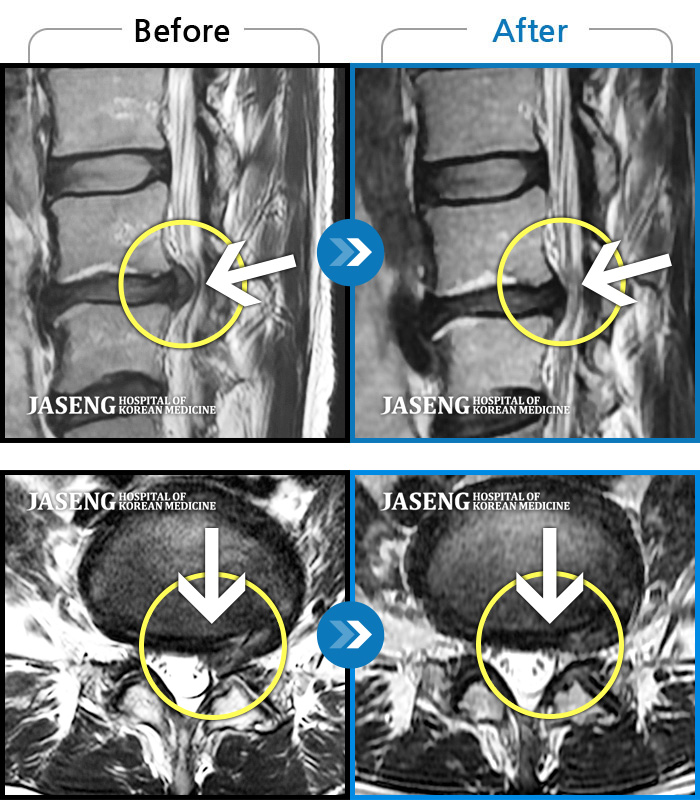

MRI로 보는 치료결과

1,169건의 MRI 전후 사진으로

터진 디스크 흡수 사례를 확인하세요.

[촬영시기:24.02.19~24.10.31]

[촬영시기:24.02.19~24.10.31]

[해운대_허리디스크] 양측 다리가 당기는데 왼쪽이 더 심해요.조회수 0 2024.11.21 -